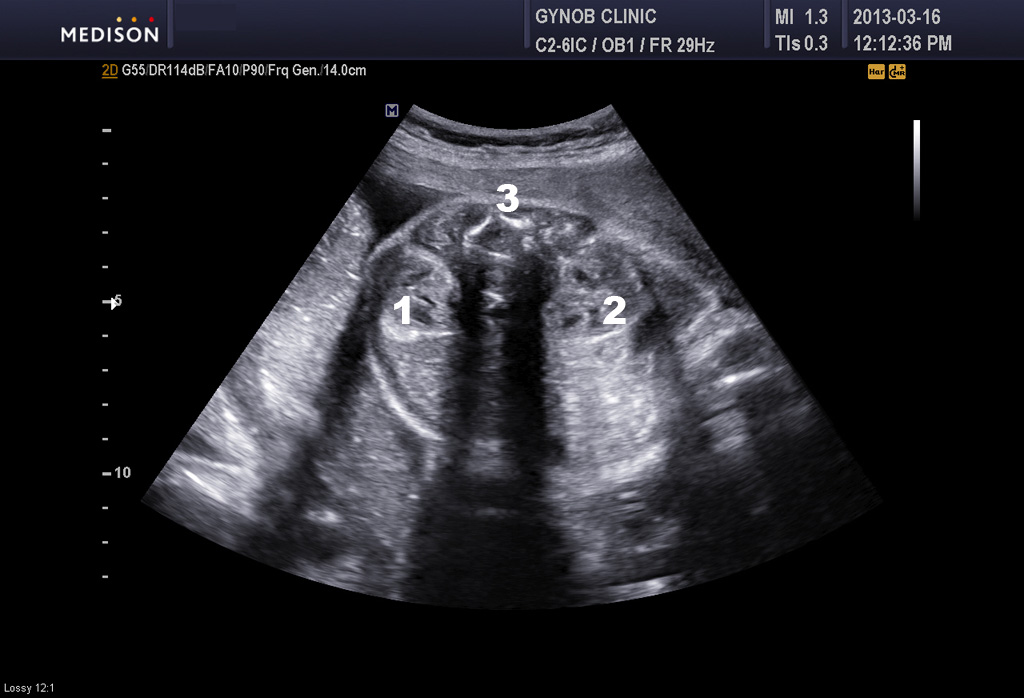

아래 사진은 본원에서 찍은 초음파 사진으로 콩팥과 방광의 정상 모습입니다.

1번과 2번은 좌우측 콩팥이며 3번은 척추 4번은 방광입니다.